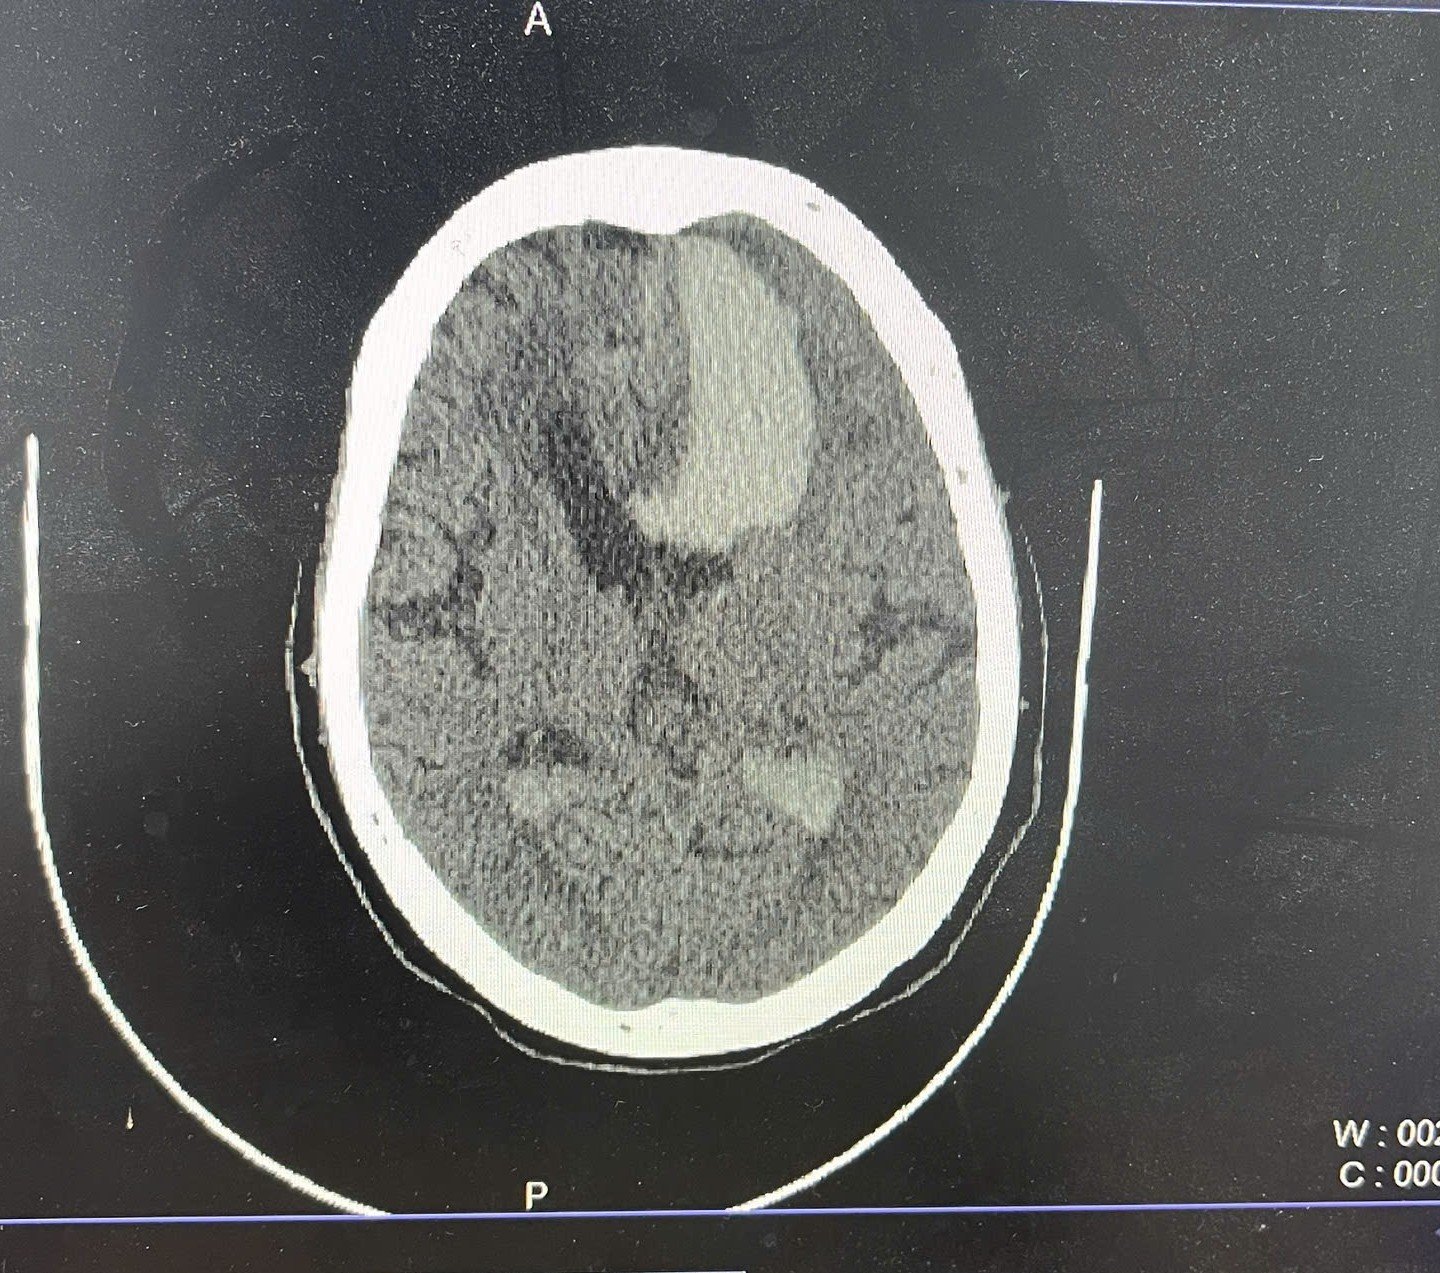

While opsoclonus-myoclonus-ataxis (dancing eye-dancing feet syndrome) may seem rare and complex, its early identification in the ED can be life‑altering. When faced with an unusual movement disorder a